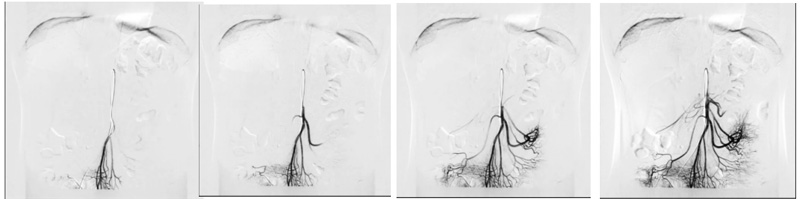

1,DSA功能

GMM OPERA FP为三类医疗器械注册证具备DSA功能,方便医院合法合规开展除心脑血管介入以外的血管和非血管介入项目。

将摇杆推动较大角度——立柱以较快的速度移动,确保大范围运动的检查效率,特别运用于下肢静脉造影的高速运动和连续采集,使得跟踪高速流动的造影剂成为可能。